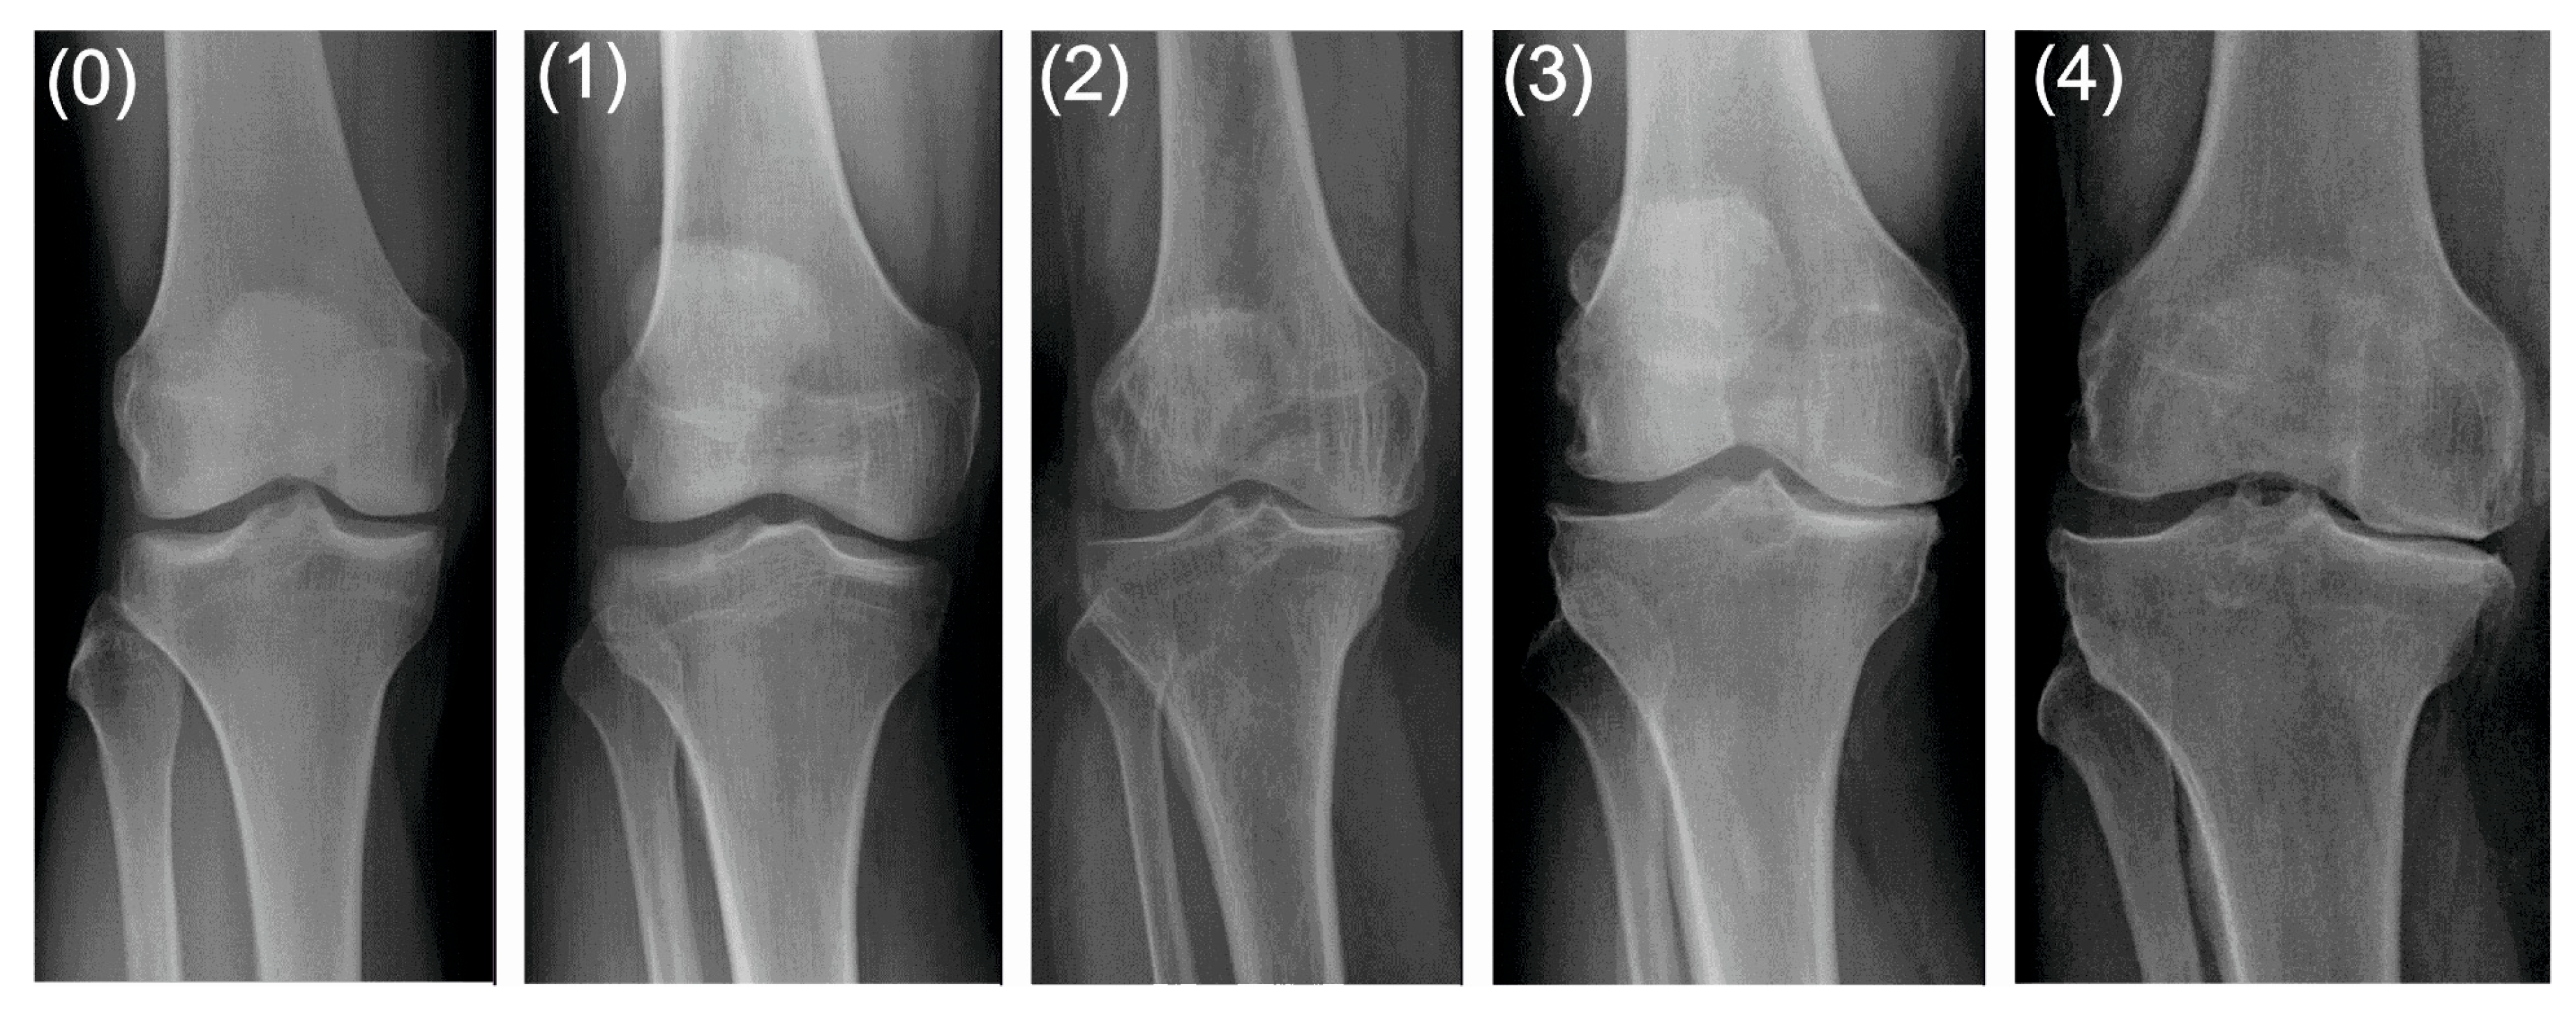

| grade 0 (none) | definite absence of X-ray changes of osteoarthritis |

| grade 1 (doubtful) | doubtful joint space narrowing and possible osteophytic lipping |

| grade 2 (minimal) | definite osteophytes and possible joint space narrowing |

| grade 3 (moderate) | moderate multiple osteophytes, definite narrowing of joint space and some sclerosis, and possible deformity of bone ends |

| grade 4 (severe) | large osteophytes, marked narrowing of joint space, severe sclerosis and definite deformity of bone ends. |